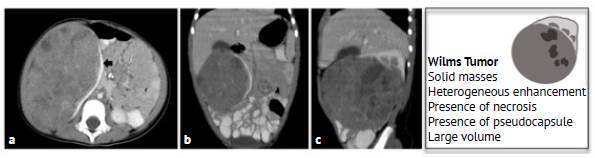

All Wilms tumors were characterized as solid masses (100%), 48.78% were larger than 10 cm, heterogeneous enhancement was observed in 95.12%, necrosis was present in 87.80%, and the presence of pseudocapsule was observed in 82.92%. Figure 1 shows the CT scans of a Wilms tumor in one of the patients included in the study to illustrate the typical features of a Wilms tumor.

Wilms tumor in a 1-year-old girl. Contrast-enhanced CT scan of the abdomen: axial (a), coronal (b) and sagittal (c) planes. >10 cm right renal solid mass with heterogeneous enhancement and areas of lower density due to necrosis. Pseudocapsule formed by spared renal parenchyma (black arrow on figure 1.a). The characteristics of Wilms tumors are summarized in the illustration

Figure 1: Wilms tumor in a 1-year-old girl. Contrast-enhanced CT scan of the abdomen: axial (a), coronal (b) and sagittal (c) planes. >10 cm right renal solid mass with heterogeneous enhancement and areas of lower density due to necrosis. Pseudocapsule formed by spared renal parenchyma (black arrow on figure 1.a). The characteristics of Wilms tumors are summarized in the illustration

Source: Picture Archiving and Communication System of the Radiology Service of the Fundación Hospital Pediátrico La Misericordia. Illustration: own elaboration.